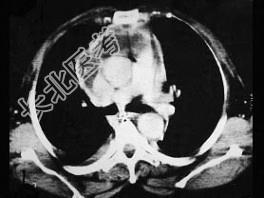

- 单项选择题男,64岁, 患糖尿病,最近三天出现发热, 伴颈静脉显露,结合CT图像, 选择最可能的诊断 ( )

A、坏死性纵隔炎

B、纵隔淋巴瘤

C、侵袭性胸腺瘤

D、恶性畸胎瘤

E、纵隔脓肿